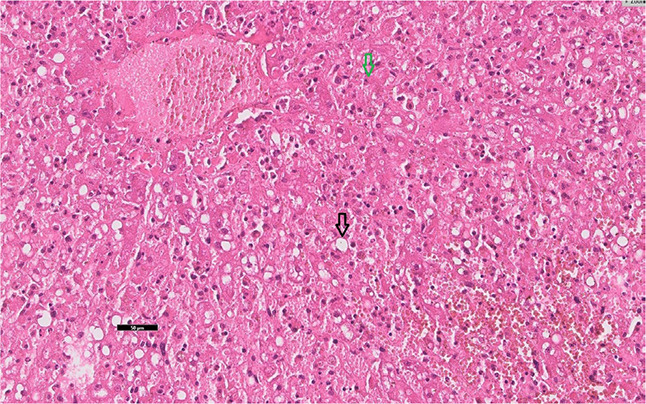

本研究描述了一匹马的吡咯里西啶生物碱中毒病例。据作者所知,这是首例确诊的蛇莓中毒病例。一匹 6 岁、体重 450 千克的爱尔兰驹母马因出现肝性脑病症状而被送往布尔诺兽医大学(捷克)马科诊所,尽管接受了强化治疗,但病情仍随时间推移而逐渐恶化,最终导致安乐死。本文介绍了一种复杂的诊断和治疗方法,包括死后病理解剖学和组织病理学检查。在肝脏组织病理学方面,肝脏坏死并伴有出血、脂肪变化和炎症。随后对放牧区进行的检查发现了木豚草(Senecio ovatus)的存在。采用灵敏的色谱法测定了血浆和肝脏中的吡咯烷生物碱及其代谢物。在两个样本中都检测到了吡咯里西啶生物碱的代谢物。虽然证明了吡咯里西啶生物碱中毒,但却没有这种疾病的典型组织病理学结果。从我们的病例中可以清楚地看出,吡咯里西啶类生物碱中毒病例的组织病理学检查并不总是确凿无疑的。

This study describes a case of poisoning by pyrrolizidine alkaloids in a horse. To the best of the author's knowledge, this is the first confirmed case of Senecio ovatus poisoning. A six-year-old 450-kg Irish cob mare was presented to the Equine Clinic of the University of Veterinary Sciences Brno (Czechia) with symptoms of hepatic encephalopathy, which progressively worsened with time despite intensive therapy and led to euthanasia. A complex diagnostic and therapeutic approach including the post-mortem patoanatomical and histopathological examination is described here. Regarding the histopathology of the liver, there was necrosis with haemorrhage, fatty changes and inflammation. A later inspection of the grazing area revealed the presence of Senecio ovatus (wood ragwort). A sensitive chromatographic method was used to determine the pyrrolizidine alkaloids and their metabolites in the plasma and the liver. In both of the samples, metabolites of pyrrolizidine alkaloids were detected. Although pyrrolizidine alkaloid poisoning was proven, the histopathological findings typical for this disease were absent. It is clear from our case that the histopathology in cases of poisoning by pyrrolizidine alkaloids may not always be conclusive.